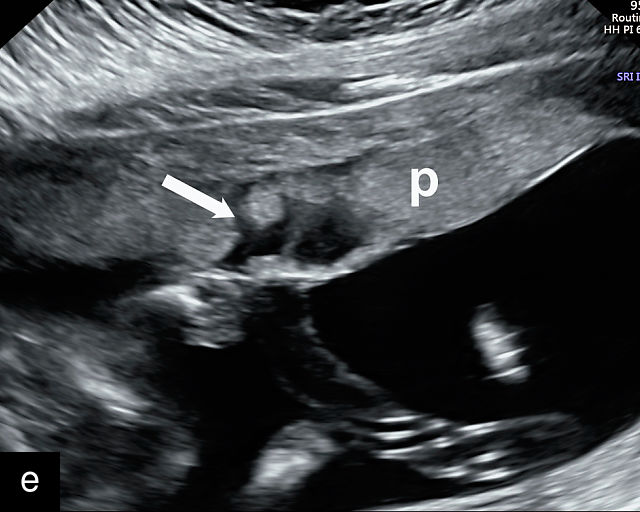

Placenta previa and low-lying placenta

In most pregnancies, the placenta implants in the upper part of the uterus. However, when the placenta implants in the lower uterine segment and overlies the cervix, it results in a condition called placenta previa, meaning the placenta is positioned ahead of the fetus in the birth canal.49 This positioning poses a serious risk during labor, as cervical dilation can cause premature placental separation, leading to severe, life-threatening bleeding for the pregnant patient.50,51 To prevent this hemorrhage, patients with placenta previa must be delivered by cesarean section before the onset of labor.51 Placenta previa complicates approximately 0.4% (1 in 250) of pregnancies at delivery.52 The strongest risk factor for placenta previa is a history of prior cesarean delivery.53,54,55 Maternal smoking, advanced maternal age and assisted reproductive technologies are also strong risk factors for placenta previa.56,57,58,59

Historically, placenta previa was most often identified in the early third trimester when patients presented with painless vaginal bleeding.49,60,61 However, with the widespread use of obstetric ultrasound in the second trimester, nearly all cases of placenta previa are now diagnosed incidentally in asymptomatic patients during routine scans. Notably, approximately 90% of placenta previa cases diagnosed in the second trimester will resolve by term due to placental ‘migration’ as the uterus grows.51,61,62,63,64,65 Thus, when placenta previa is diagnosed in the second half of pregnancy, the patient should have an examination close to delivery to determine whether the placenta previa is persistent or whether it has resolved. Generally, when a placenta previa is found at 20 weeks, a repeat ultrasound should be performed at about 32 weeks. In cases that persist at 32 weeks, a repeat scan should be performed around 36 weeks of gestation.66

In the past, placenta previa was classified as complete, partial, marginal or low-lying.50,61 However, with advancements in ultrasound technology allowing precise assessment of the relationship between the placenta and the internal cervical os, the classification has been simplified.67 Placenta previa now refers to cases in which the placenta overlies the internal os to any degree, while low-lying placenta describes cases in which the lower placental edge lies within 2 cm of the internal os (Figure 5).51,66,67

This distinction is critical in determining the mode of delivery.49,51 All patients with placenta previa persisting into late pregnancy require cesarean delivery to avoid complications such as severe bleeding.50,60,61 Studies suggest that patients with a lower placental edge located more than 1 cm from the internal os may safely attempt a vaginal delivery without a significant increase in bleeding risk.68,69,70,71

In patients with placenta previa and one or more prior cesarean deliveries, careful evaluation is necessary to rule out placenta accreta spectrum disorders, in which the placenta abnormally adheres to or implants deeply into the uterine wall.50,60

Most cases of placenta previa will be suspected prenatally by transabdominal ultrasound.49 However, this approach has several limitations and may be inaccurate.72,73,74 because the relationship between the placenta and the internal cervical os may be difficult to assess by transabdominal ultrasound.72,73,74 The bladder may be full, pushing the anterior and posterior walls of the lower uterine segment together, falsely creating the impression of a placenta previa (Figure 5e).61 There may be considerable shadowing, including by the fetal presenting part, which may limit the accuracy of transabdominal ultrasound (Figure 5d,f).75 Posterior placentas may be more difficult to assess.

Transvaginal ultrasound overcomes these limitations (Figure 5g–l).72,73,74,76 The probe is inserted into the vagina and therefore is closer to the region of interest.51,61 In addition, transvaginal transducers have higher frequencies and superior resolution compared to transabdominal transducers. Transvaginal ultrasound is safe and is not associated with increased bleeding.72,73,74,75,76 As such, transvaginal ultrasound should be the imaging modality of choice whenever there is suspicion of placenta previa.49,67,77